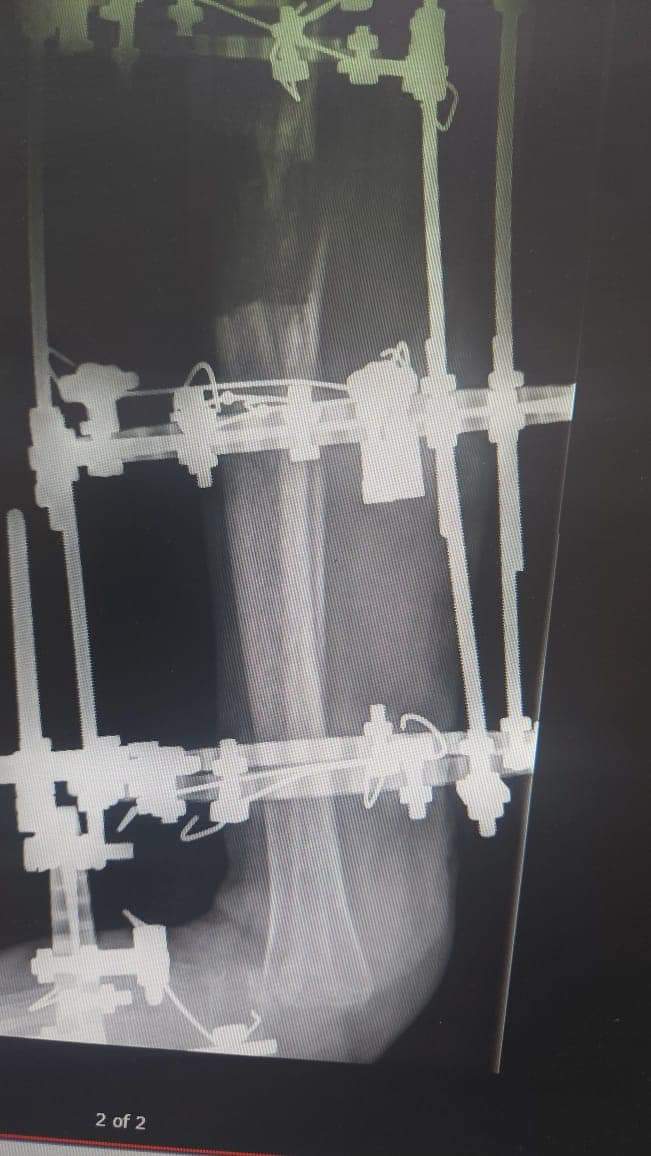

أجرى فريق طبي متخصص من دائرة العظام برئاسة أخصائي أول جراحة العظام المقدم الطبيب بسام الحراحشة عملية نوعية وهي الأولى من نوعها على مستوى المملكة تم فيها ترميم قدم فتاة تبلغ من العمر ١٩ عام بعد إصابتها بإلتهاب مستعصي في عظام القدم والكاحل بعد استنفاذ كل الطرق التقليدية في علاجها .

وقال المقدم الطبيب الحراحشة ان الفتاة راجعت عيادة العظام وعند التشخيص تبين وجود إلتهاب شديد في عظام الكعب والكاحل ،فتقرر بعد ذلك تحويل الفتاة إلى عيادة ترميم الأطراف لعلاجها بطريقه مبتكرة دون الحاجة إلى بتر القدم .

وبين المقدم الطبيب الحراحشة ان العملية اجريت على مرحلتين الأولى تم خلالها استئصال الأجزاء المصابة والمرحلة الثانية تم ترميم عظام القدم والكاحل عن طريق عظام الساق السليمة وتحويل جزء من عظام الساق لتحل مكان الجزء المستأصل من القدم مع إعادة تشكيلها بشكل ينسجم مع شكل القدم ويستطيع المشي عليها.